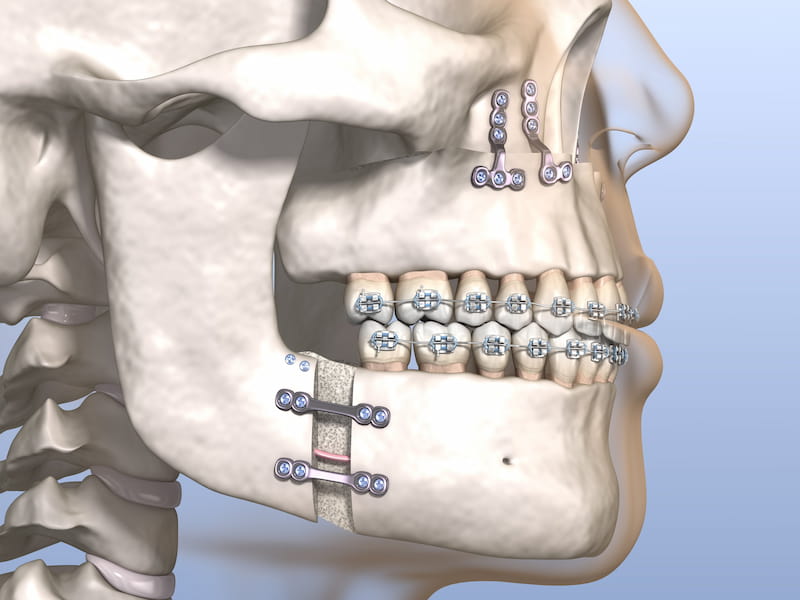

در حوزه زیبایی چهره، یکی از راههای محبوب برای بهبود شکل فک و دندانها، استفاده از ایمپلنت فک کامل میباشد.

مشخصات ایمپلنت فک کامل

ایمپلنت فک کامل، راهی عالی برای جایگزین کردن دندانهای گمشده است و باعث تقویت قوس های فکی و بهبود خط بندی نیز میشود.